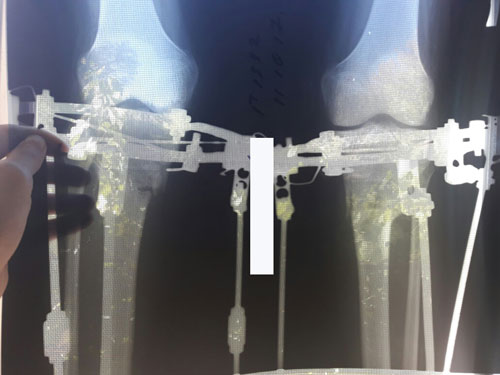

РЕНТГЕН ДО ОПЕРАЦИИ